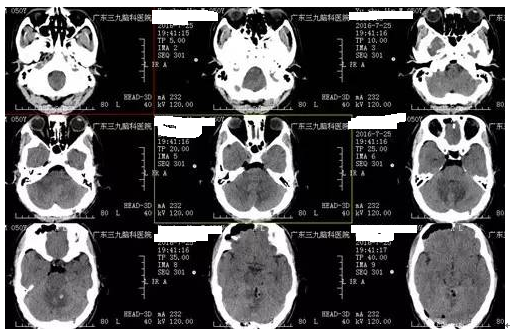

↑术后CT

间变型星形细胞瘤治疗为手术、放疗、化疗等的综合治疗,直视下全切除极为困难。有研究表明,根治性切除和部分切除两组的5年肿瘤无进展生存率分别为(44±11)%和(22±6)%,因此手术应争取全切除。本例患者病变位置较深,与脑干关系密切,术后MR示病变基本全切除,术后恢复良好,眩晕症状缓解,未有明确并发症。